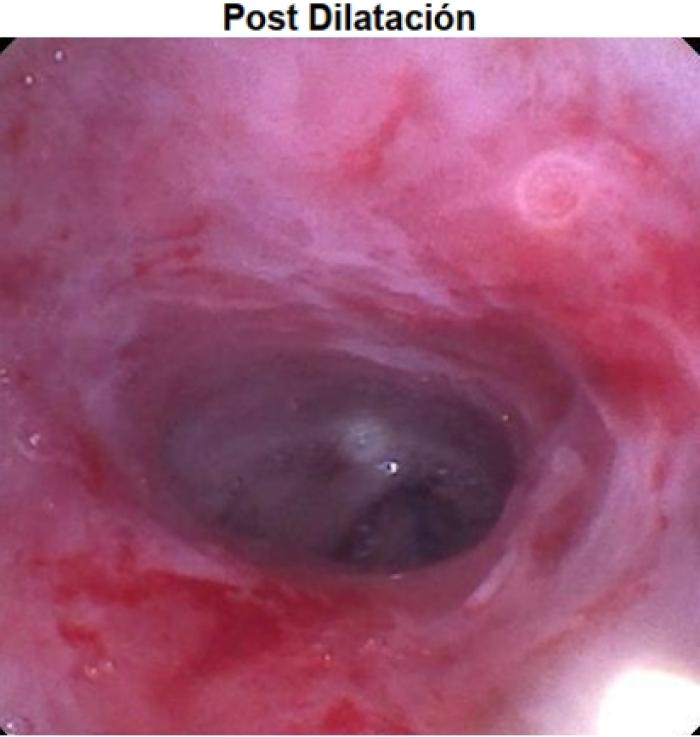

Durante el mismo procedimiento, se realizó la dilatación de la estenosis mediante un balón de 10 mm de diámetro, con cuatro aplicaciones consecutivas durante un minuto cada una (Vídeo 5).

Y dilatando la nasofaringe como se puede observar (Vídeo 6 y Figura 6).

Vídeo 6. Estenosis nasofaríngea posdilatación.

Durante el mismo procedimiento, se realizó la dilatación de la estenosis mediante un balón de 10 mm de diámetro, con cuatro aplicaciones consecutivas durante un minuto cada una, dilatando la nasofaringe.